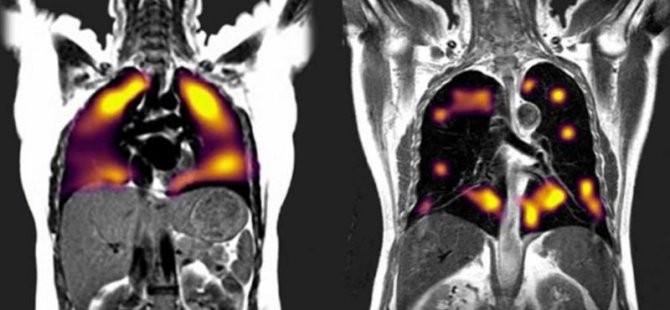

Özel bir sistemle çekilen röntgende solda sağlıklı bir akciğerin kanı nasıl dolaşıma soktuğu görülüyor. Sağda ise corona virüsüne yakalanmış bir bireyin sonuçları yer alıyor. Burada geniş siyah bölgeler kanın vücutta dolaşmadığını gözler önüne seriyor.

KAN AKIŞINI GÖSTERİYOR

Ksenon gazıyla yapılan taramalarda ise bu hastalarda akciğer hasarı belirtilerine rastlandı. Kana rahat oksijen akışı olmayan bölgeler tespit edildi. Gleeson, taramalar sonucunda hastalarda ortaya çıkan hasar boyutunun beklediklerinden fazla olduğunu kaydetti.